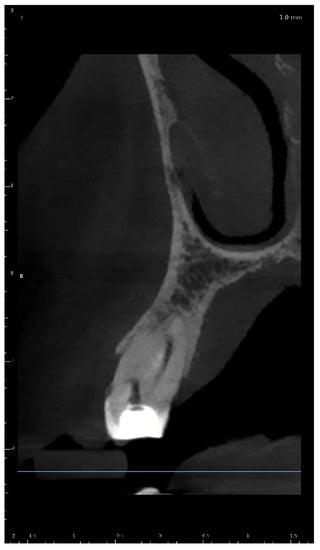

A 21-year-old female patient reported to the endodontic specialist complaining of moderate pain upon percussion of her maxillary central left incisor (tooth 21), experienced for several weeks. The patient was healthy and had no general or chronic diseases. Her dental history revealed that she had experienced dental trauma a few years earlier. The clinical examination revealed a slightly discoloured maxillary left central incisor, tenderness to percussion, a negative response to the pulp sensibility test (cold test), and moderate pain during soft tissue palpation in the apical region of the maxillary central left incisor. Radiographic images revealed the pulp canal calcification and an absence of the canal light that extended to the middle. A CBCT scan was performed (CS 8100 3D, Carestream, 50 × 50 mm) that confirmed canal calcification. The root canal lumen was visible 7.58 mm from the apex (Figure 8). Due to the possible risk of higher tooth substance loss and perforation during endodontic access, we decided to perform the endodontic treatment with guided access.

Figure 8. CBCT sagittal view image revealed a 7.58-mm-long visible part of the root canal on tooth 21 (FDI).